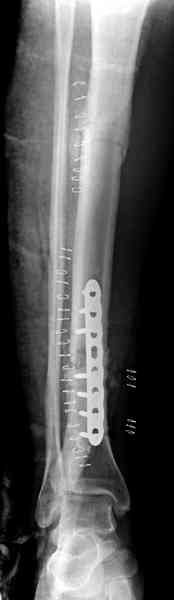

Недавно на нашей ежемесячной Morbidity&Mortality conference мы

разбирали похожий случай, ложный сустав большеберцовой кости после

резекции опухоли.

Оперирован в военном госпитале с заменой сегмента аллокостью

большеберцовой кости и после демобилизации явился для постоянного

наблюдения по месту жительства.

Наши имели проблему со сращением, пришлось им сделать динамизацию,

дополнительную аутопластику.

Снимки представлены.

Имя     : 4 adamantioma ap.jpg